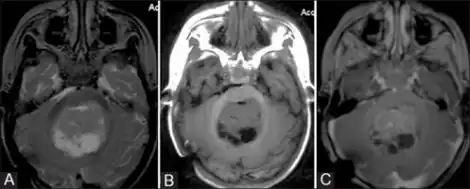

| MRI of an AT/RT | |

Appearance on radiologic exam

AT/RTs can occur at any sites within the CNS; however, about 60% are located in the posterior fossa or cerebellar area. The ASCO study showed 52% posterior fossa; 39% sPNET; 5% pineal; 2% spinal, and 2% multifocal.[1]

The tumors' appearance on CT and MRI are not specific, tending towards large size, calcifications, necrosis (tissue death), and hemorrhage (bleeding). Radiological studies alone cannot identify AT/RT; a pathologist almost always has to evaluate a brain tissue sample.

The increased cellularity of the tumor may make the appearance on an uncontrasted CT to have increased attenuation. Solid parts of the tumor often enhance with contrast MRI finding on T1 and T2 weighted images are variable. Precontrast T2 weighted images may show an isosignal or slightly hypersignal. Solid components of the tumor may enhance with contrast, but not always. MRI studies appear to be more able to pick up metastatic foci in other intracranial locations, as well as intraspinal locations.

Preoperative and follow-up studies are needed to detect metastatic disease.